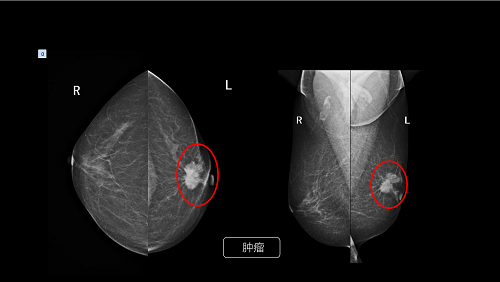

(乳腺肿瘤显示图像)

目前,X 线摄影检查是乳腺疾病的有效诊断方式之一,能够及时发现乳腺组织中的肿块及微小的钙化点,为乳腺疾病治疗提供有效诊断依据。“芳华”在微小钙化的检出及识别上有独特的优势。搭载的是24cm x 30cm大尺寸高清数字平板探测器,相较于以往18CM x26CM小型乳腺平板探测器,能满足各种乳腺尺寸的摄影要求,能有效的覆盖到淋巴区域,在同一张乳腺平片上显示更多的信息与细节。不仅如此,芳华平板还具有更好的线性响应和宽阔的动态范围, 具备1200万以上超高清像素,能精准识别毫米级别的微小钙化病灶与肿块病灶。